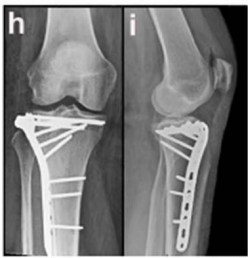

Caso clínico para responder à questão.

Um paciente de 39 anos de idade, vítima de queda de bicicleta, sofreu trauma no joelho direito. Foi levado ao pronto-socorro do hospital mais próximo, onde foram realizadas as radiografias apresentadas.